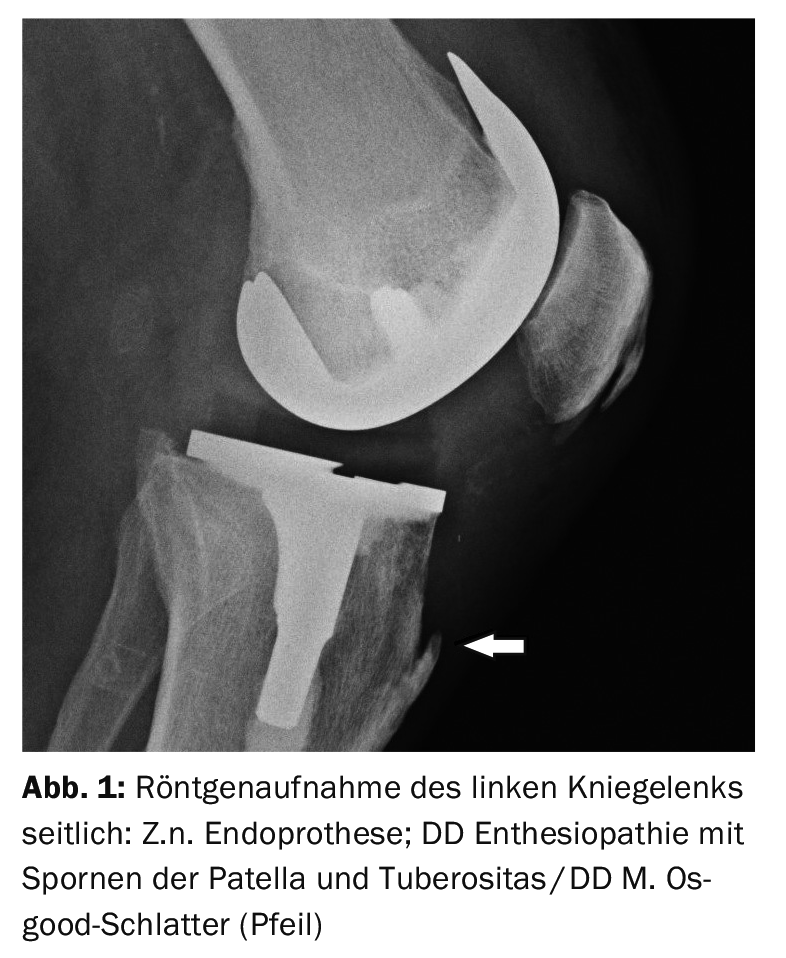

Radiographs in lateral projection can document the bony deformities of the tibial tuberosity very well, but do not tell us anything about the extent of local soft tissue inflammation or bony irritation. Computed tomographic studies, particularly sagittal 2D reconstruction of axial scans, demonstrate the bony changes of Osgood-Schlatter disease. However, soft tissue contrast is significantly reduced compared to MRI and thus local inflammation of the patellar tendon, bursitis, or Hoffitis may escape detection.

In case report 1, a lateral radiograph of the left knee joint (Fig. 1) for control after prosthesis implantation in a 79-year-old patient shows a bone spur at the attachment of the patellar tendon with palpable bony resistance, image morphologically not the typical situation of old Osgood-Schlatter disease. Case report 2 shows an initialOsgood-Schlatter‘s disease in a 13-year-old boy (Fig. 2) with spongiosa edema with preserved shape and contour, accompanied by perifocal soft tissue inflammation. Case example 3 demonstrates an avital fragment (Fig. 3) of the tuberosity in a 16-year-old adolescent already suffering from Osgood-Schlatter disease with local soft tissue inflammation.